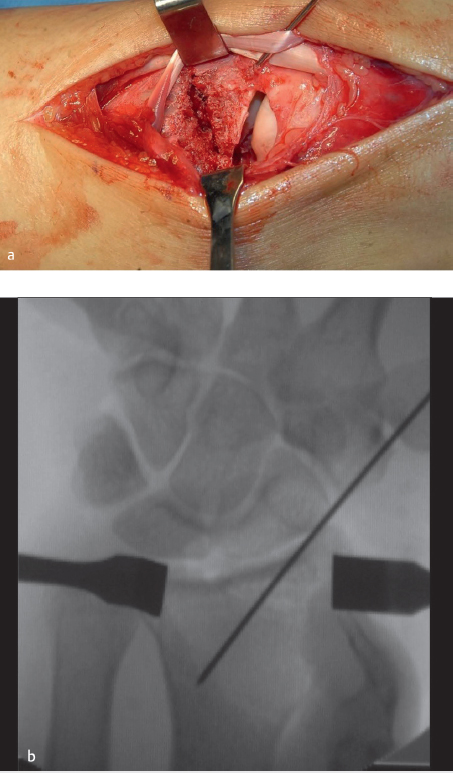

A 30 y/o male sustained a fall from a height and presented with right distal radius fracture. PA and lateral radiographs revealed a complex radiocarpal fracture-dislocation of his right wrist (► Fig. 44.3). Sagittal, two-dimensional CT views demonstrate the very small shearing fracture of the dorsal aspect of the distal radius with dislocation of the carpus (► Fig. 44.3).

Three-dimensional CT reconstructions show the volar rim of the radius to be intact with the dorsal small shearing fracture fragments (► Fig. 44.3). Also seen in all the preoperative images is the radial styloid fracture. Notice the horizontal fracture line involving the entire scaphoid fossa and continuing to the dorsal cortical rim. Operative fixation was recommended. A standard dorsal approach to the wrist was used, with a longitudinal incision over distal radius and radiocarpal joint in line with the 3rd metacarpal. The extensor pollicis longus tendon was mobilized from the 3rd dorsal compartment and the tendons of the second and fourth dorsal compartment were retraced to gain exposure (► Fig. 44.4). The dorsal small rim and the radial styloid fractures are clearly visualized. Usually the capsule is torn (► Fig. 44.4), but if it is intact, a dorsal arthrotomy is made parallel to the dorsal rim to inspect the articular surface and look for any associated carpal injury. At this point, carpus is reduced and fixation is started with the less comminuted fracture fragment. In this case, a 0.062 smooth K-wire was used for provisional fixation of the radial styloid fracture, and articular reduction was also confirmed using intraoperative fluoroscopy (► Fig. 44.4). If dorsal rim fragments are adequately large, provisional fixation can be obtained with K-wires. If they are too small, they can be held with suture anchors or transosseous sutures. Low-profile dorsal-distal radius plates were then used for fragment-specific fixation (► Fig. 44.5). Radial column plate and 2.4 mm dorsal plate were used. Capsule was repaired using resorbable suture (► Fig. 44.5). Follow-up at 8 months showed excellent function with some loss of wrist extension and flexion (► Fig. 44.6). Many plates are available for these fractures. The most recently designed plates have variable angle locking screws. The dorsal plate should be applied as distally as possible. These plates might need some contouring to fit the distal radius metaphysis and the radial styloid.